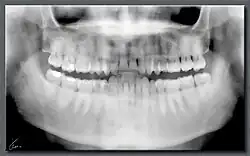

Ortopantomografía

La ortopantomografía o radiografía panorámica es una técnica radiológica que representa, en una única película, una imagen general de los maxilares, la mandíbula y los dientes. Por tanto, es de primordial utilidad en el área dentomaxilomandibular.

Su papel en el diagnóstico odontológico, no solo de los dientes sino también del maxilar y mandíbula, es fundamental. Sin la ortopantomografía, el odontólogo perdería una gran ayuda en la mayoría de las especialidades de su campo. Prácticamente, es utilizada de forma sistemática en odontología, llegando a ser un arma diagnóstica rutinaria. El valor diagnóstico de la ortopantomografía en cirugía bucal, implantología, ortodoncia, periodoncia y en patología oral y dental está claramente demostrado.

El término de radiografía panorámica es el más comúnmente utilizado, ya que la radiografía resultante muestra una visión panorámica de la cara y parte inferior de la cabeza. Laudenback describe la ortopantomografía como uno de los inventos radiológicos más originales de los últimos decenios. El 40 % de los hallazgos patológicos principales y secundarios se descubren a partir de ella. Amplía el campo de diagnóstico en un 70 % y reduce la dosis de radiación de la superficie cutánea en un 90 % con respecto a las series radiográficas periapicales.